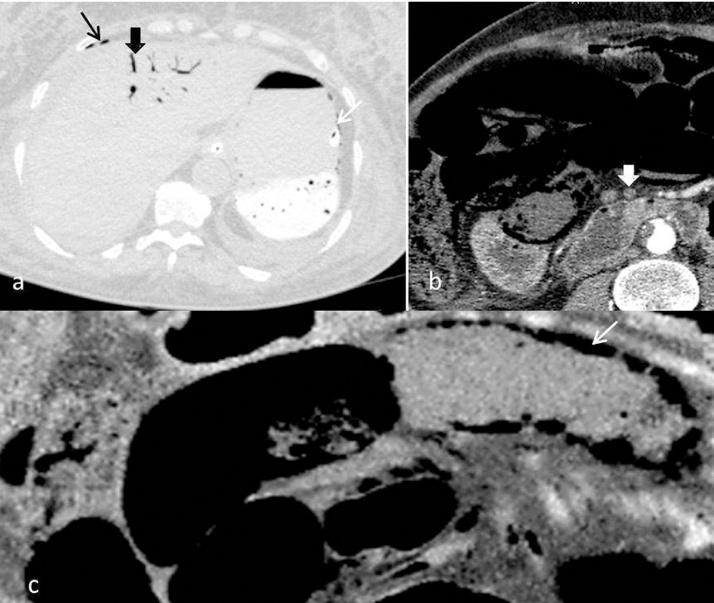

Etiologies were mesenteric infarction (n=5), sigmoid diverticulitis (n= 1), septic shock (n=1), postoperative peritonitis (n=1), acute pancreatitis (n=1), iatrogenic cause (n=3) and idiopathic after a laparotomy (n=1). The outcome was fatal in for 6 patients. Abundance of HPV was expressed in total number of hepatic segments involved. The involvement of 3 or more segments was a sensitive sign for lethal outcome with high sensitivity (100%) but it was not specific (50%). Negative predictive value of this sign was 100% (p≤0.005). Positive predictive value of PI for death was 100% (p≤0.001).

DISCUSSION

Abundance of HPVG is correlated with prognosis. The presence of PI announces poor outcome Negative predictive value of presence of HPVG in 3 or more segments is interesting. Predicting prognosis with CT can help surgeons to assess the most adequate treatment. Iatrogenic causes are increasingly described after interventional radiology procedures with favorable course.

The first etiology radiologists should look for in front of HPVG involving more than 3 hepatic segments and associated with PI is intestinal necrosis which announces a poor prognosis. This study shows that outside of shock situations, HPVG involving 2 or less hepatic segments without PI predicts a good outcome.

病因包括肠系膜梗死(n = 5)、乙状结肠憩室炎(n = 1)、感染性休克(n = 1)、术后腹膜炎(n = 1)、急性胰腺炎(n = 1)、医源性原因(n = 3)和剖腹术后特发性(n = 1)。6例患者预后为致命。HPV的丰度以受累肝段总数表示。3个或更多肝段受累是致命结局的敏感征象,敏感性高(100%)但不具有特异性(50%)。该征象的阴性预测值为100%(p≤0.005)。PI对死亡的阳性预测值为100%(p≤0.001)。

讨论

对于累及3个以上肝段且伴有PI的HPVG,放射科医生首先应寻找的病因是肠坏死,这预示着预后不良。本研究表明,在非休克情况下,累及2个或更少肝段且无PI的HPVG预示预后良好。